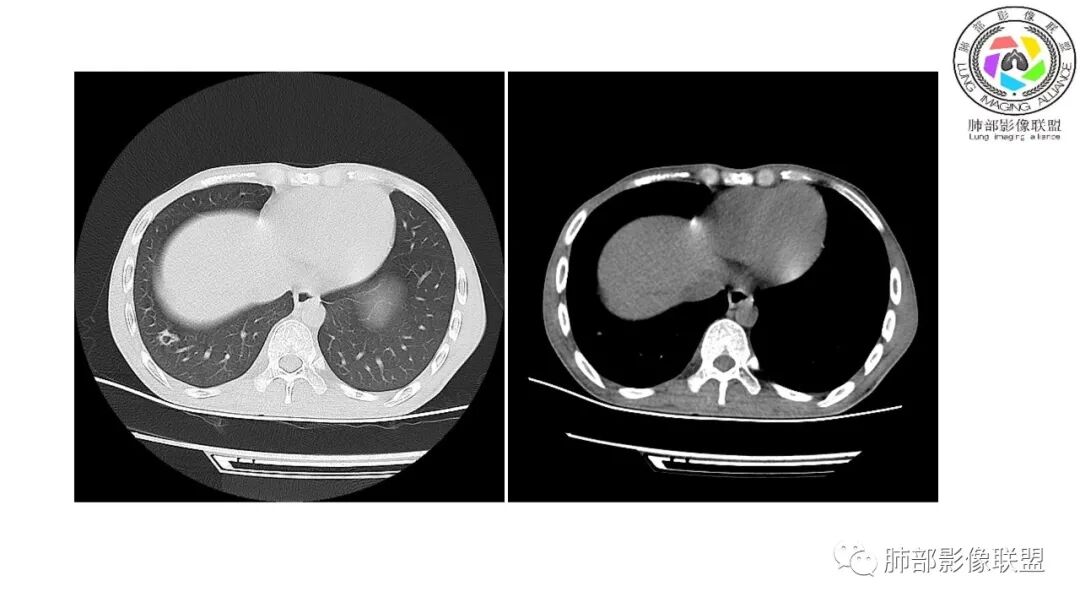

影像与临床:1.青年男性,HlV阳性,颜面部皮疹(未提供皮疹图像)、发热(高热),实验室CRP、PCT高,T-Spot阴性。2.右肺下叶空洞结节,壁厚不均,边界清楚,其内线状影,未见液平及钙化,未见卫星灶,纵隔淋巴结增大,双侧腋窝见增大淋巴结。心腔内低密度提示贫血可能。肝脾影增大,未见结节影及块影。腹膜后见多发增大淋巴结。

综合分析:本例肺部影像学改变并不具有特征性,空洞性病灶须与多种疾病鉴别,但年轻HIV阳性患者,高热,皮疹,肝脾增大,纵隔、腋窝、腹膜后见多发增大淋巴结等都强烈提示马尔尼菲篮状菌感染的可能性。